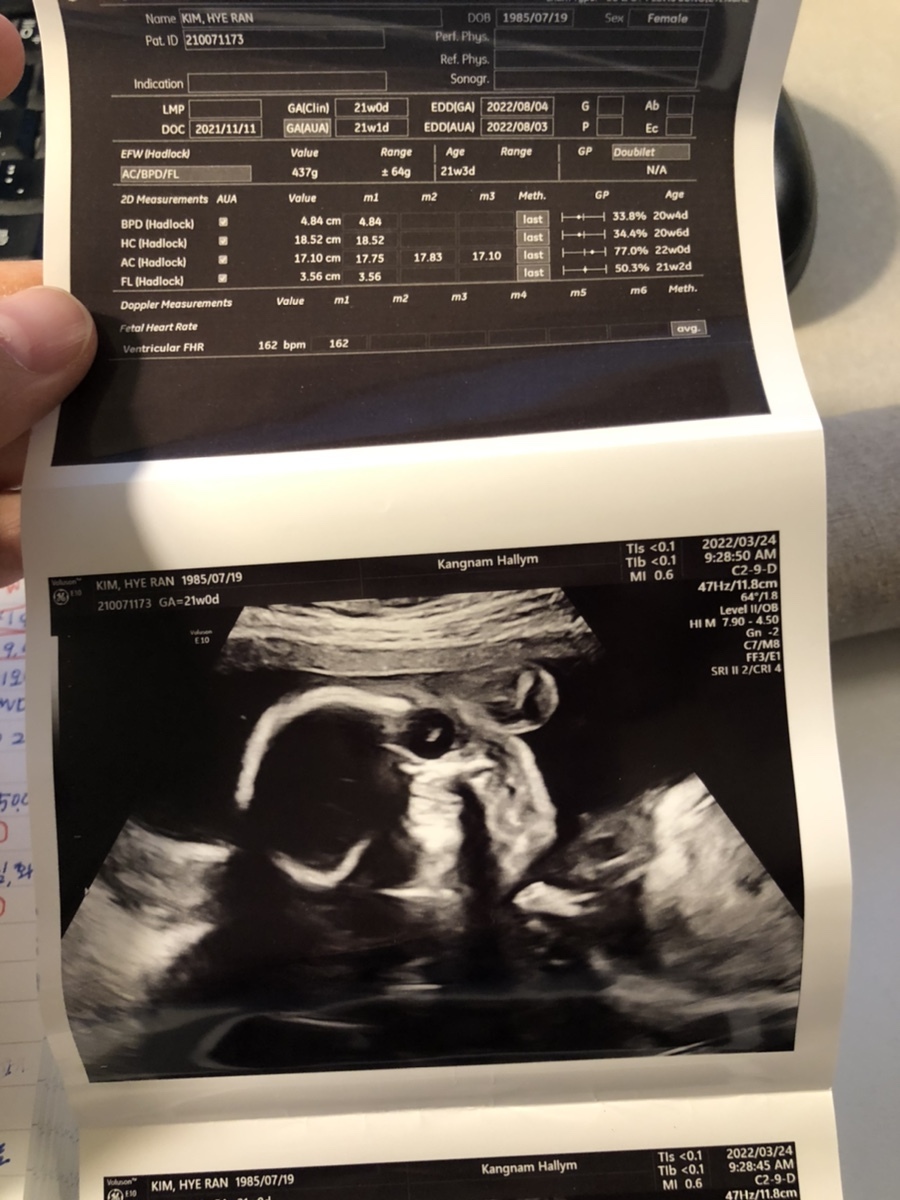

3월 24일 목요일(21주차 1일)

BPD(Biparietal Diameter, 위에서 볼 때 태아 머리 단면의 가장 긴 길이): 4.84cm

HC(Head Circumference, 태아 머리둘레): 18.52cm

AC(Abdominal Circumference, 배 둘레): 14.86cm

EDD(Expected Date of Delivery, 출산 예정일): 2022년 8월 4일

FL(Femur Length, 허벅지뼈 길이): 3.56cm

GA(Gestational Age, 임신 주차): 21주 차 1일

EFW(Estimated Fatal Weight, 태아 예상 체중)=EBW(Estimated Body Weight): 437g

FHR(Fetal Heart Rate, 심장박동 수): 162bpm

CL(Cervical Length, 자궁경부 길이): 정상

AF(Amniotic Fluid, 양수): 정상

원래 정밀 초음파를 보기 위한 정기검진이 있는 날이라 방문한 병원 그런데 이미 19주 차에 정밀 초음파를 해서 오늘은 그냥 일반적인 검사만 진행했다. 20주 차에 들어서면서 숨이 차고 아래쪽이 뻐근해서 걱정했는데 의사선생님이 원래 임신하면 있는 증상이라고 하니 그냥 참는 수밖에 없을 듯하다. 그리고 16주 차에 입덧이 끝나고 19주 차에 입덧으로 인해 빠졌던 몸무게가 원래대로 돌아왔고 19주 차부터 21주 차인 오늘까지 2.8kg이 쪘다. 이렇게 급격하게 살이 찌다니... 제주도 여행의 후폭풍인 건가.

초음파를 보는데 활발하게 뱃속에서 움직이던 이안이, 복부 초음파랑 질 초음파를 볼 때마다 본인 귀찮게 하지 말라는 건지 발길질을 해대는 게 선명하게 초음파 상으로 보인다. 이제 3주 뒤 임당 검사를 준비해 볼까나~